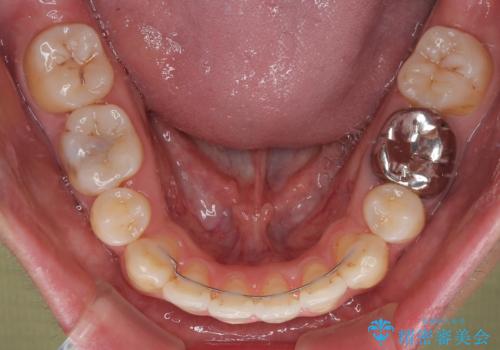

口元の突出が改善され、横顔の印象が大きく変化し、口が自然に閉じやすくなりました

前歯のデコボコが整い、清掃性が向上

噛み合わせが改善し、長期的に安定する噛み合わせに

「見た目」と「機能性」の両方を改善できた、非常に満足度の高い治療となりました。